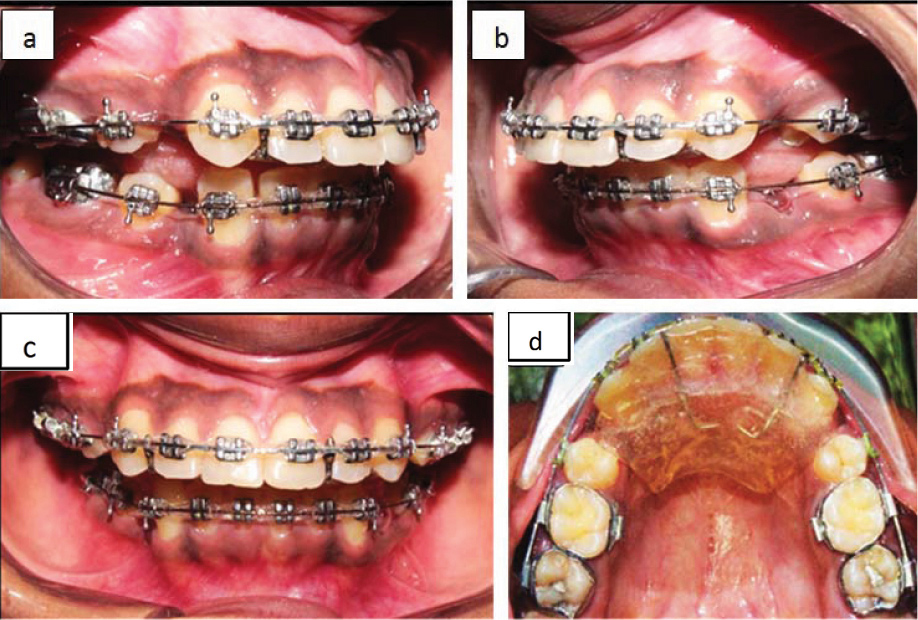

Treatment began with the upper arch bonding and an anterior bite plane was given inorder to get clearance for uprighting the mandibular molars, after reaching 16x22′ stainless steel in the upper arch [Table/Fig-11a-d].

(a,b) After delivery of the anterior bite plane in the upper arch; c,d) sufficient clearance attained to upright the mandibular molars.